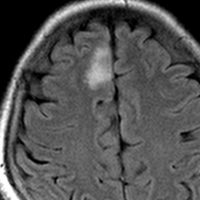

平均的な増大速度を示した乏突起膠腫グレード2です。左が無症状で発見された時,右が3年後で,ごくわずかに増大しています。開頭手術で摘出しました。

• 数年単位でゆっくり大きくなるものが多いです

• 分化度の高いグレード2のオリゴは20-30年もかかってゆっくり大きくなって症状を出すものもあります